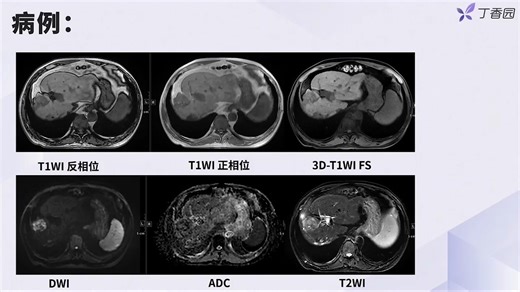

1.3 结合病例解读常见病理改变的 MRI 信号特点